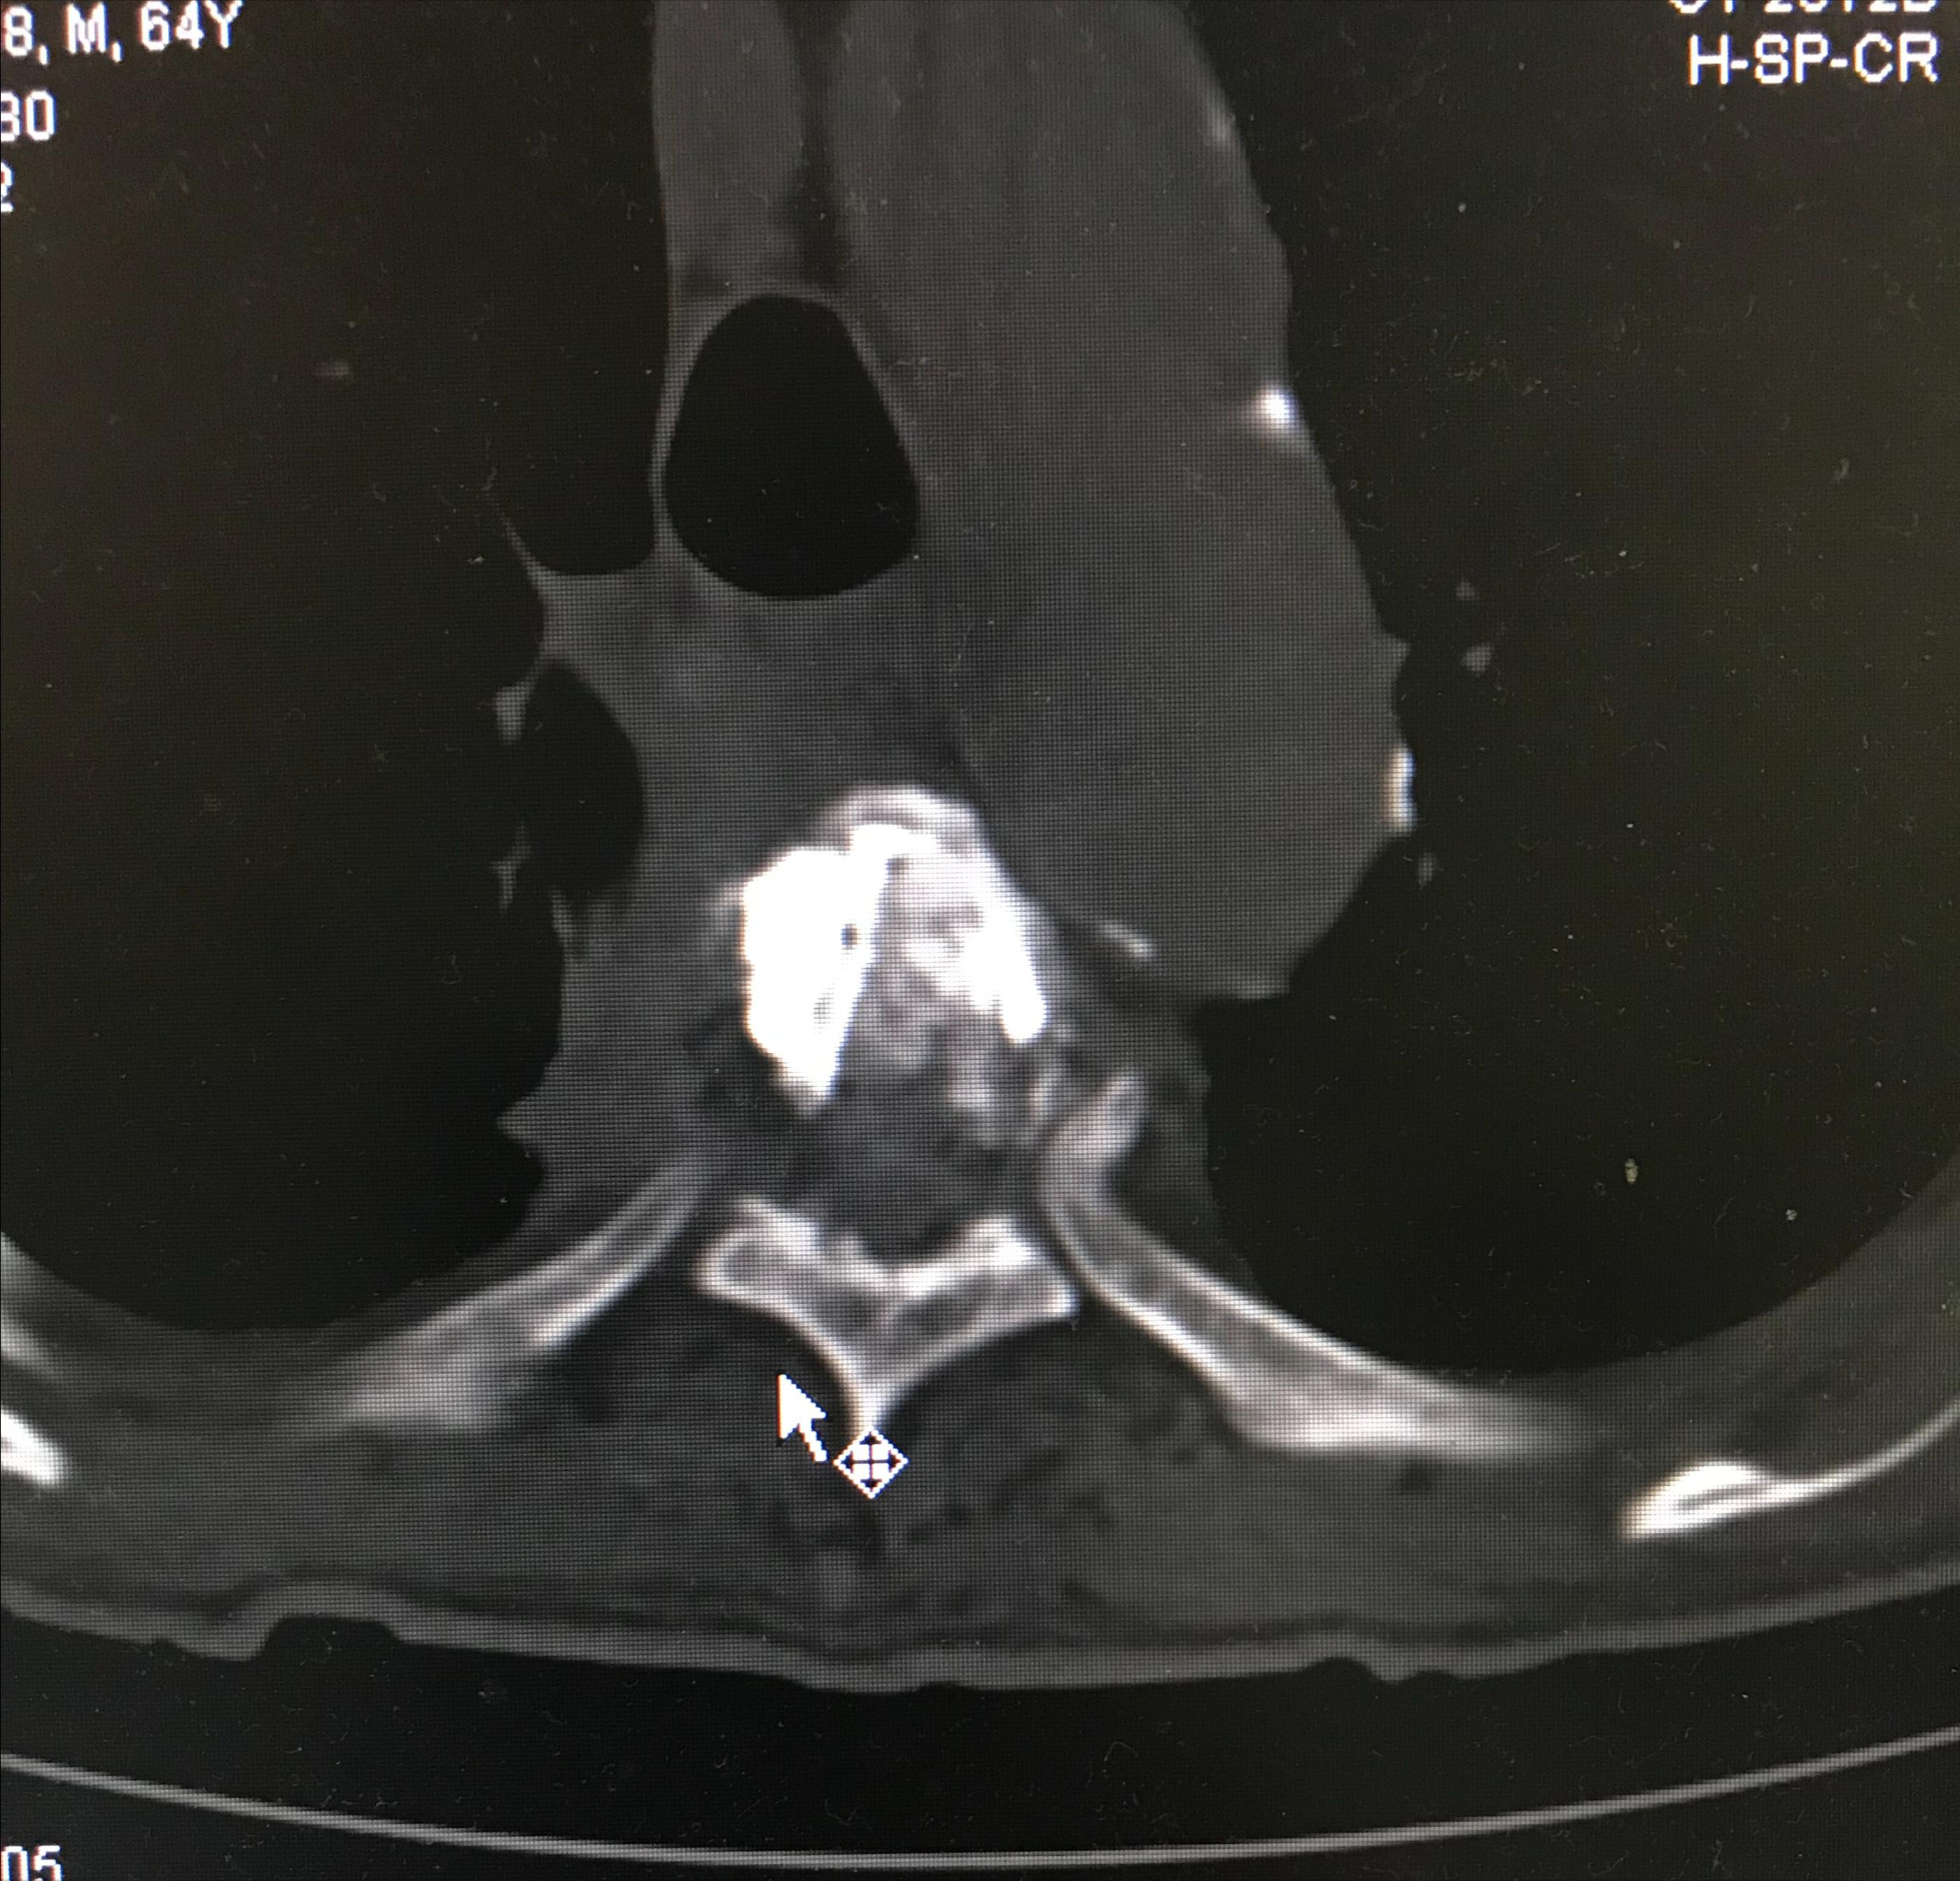

经皮椎体成形术术后进行CT扫描,重建后显示骨水泥在T5椎体内充填到位,且分布良好。

PVP术后轴位扫描显示骨水泥分布良好